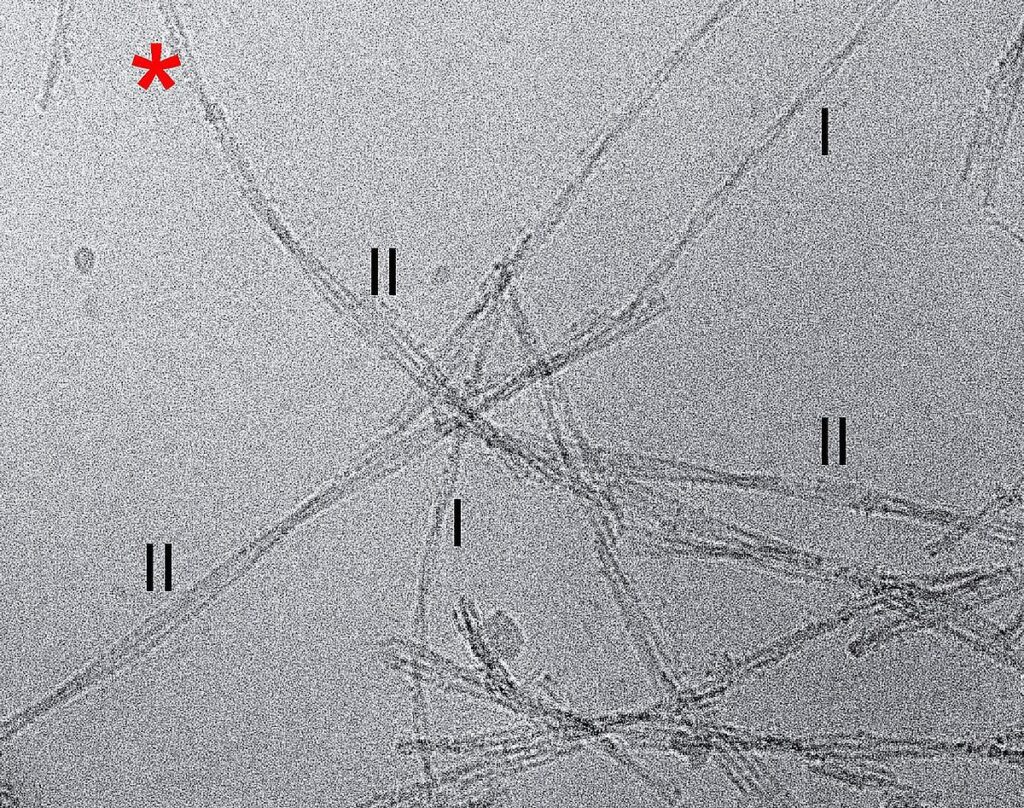

De onderzoekers ontdekten dat de vezels aanzienlijk verschillen van de synthetisch geproduceerde vezels die in het onderzoek worden gebruikt. De afzonderlijke peptiden waaruit de fibrillen bestaan, verschilden van die welke kunstmatig in de reageerbuis werden geproduceerd.

Ten tweede vertoonden de structuren een heel andere manier draaiing dan bij synthetische fibrillen. “Dit is een fundamenteel andere eigenschap, die we niet hadden verwacht”, aldus professor Marcus Fändrich, hoofd van het Instituut voor Eiwitbiochemie aan de Universiteit van Ulm. In hun studie onderzochten de onderzoekers de weefselmonsters van drie patiënten. Ze vonden bij alle drie de patiënten dezelfde structuren.

De wetenschappers uit Ulm, Tübingen, Halle an der Saale en San Diego hebben meer dan vier jaar intensief wetenschappelijk onderzoek verricht werk voordat ze tot deze conclusie konden komen. De grootste uitdaging was het verwijderen van de bèta-amyloïde fibrillen uit de weefselmonsters en deze in verschillende stappen te zuiveren. Bovendien vertoonden de fibrillen onder de cryo-elektronenmicroscoop talrijke verschillende subtypes, wat de analyse nog moeilijker maakte.

Titelfoto: Zijaanzicht van een aß-amyloïde fibril (links), doorsnede van een fibrillair vlak (midden bovenin). Het gehele fibril bestaat uit meerdere gestapelde lagen (rechtsonder); © Kollmer et al., Nature Communications